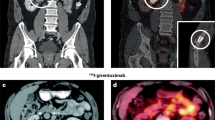

Lai, P. et al. Detection of tumour thrombus by 18F-FDG-PET/CT imaging. Eur. J. Cancer Prev. 16, 90–94 (2007).

The incidence of early and advanced-stage renal cell carcinoma (RCC) is increasing. Methods of diagnosing, staging and evaluating tumor burden that are more accurate and reliable than the currently available options are needed in order to identify RCC at a stage at which it is curable and to accurately determine the response to treatment. Functional imaging, particularly with combined PET–CT, might improve accuracy of detection and provide essential information that has been unavailable to date. This approach is against a background in which targeted therapies for metastatic RCC have entered clinical practice in the past few years, further highlighting the importance of accurate imaging for patient selection and for monitoring response to treatment. We outline the current clinical status of functional imaging in RCC using PET–CT, which allows simultaneous capture and co-registration of functional and anatomical data. New radiotracers and approaches—including radiolabeled monoclonal antibodies and imaging of tumor hypoxia—are touched on, and areas of future research discussed.

There is evidence to support a role for functional imaging using 18F-FDG-PET–CT in initial staging and re-staging of relapsing or metastatic renal cell carcinoma

Diagnostic 18F-FDG-PET–CT has limitations, but its utility might be enhanced by using immuno-PET (for example, 124I-cG250-PET–CT) or other radiolabeled molecules

Functional imaging could optimize monitoring of responses to newer therapies (for example, tyrosine kinase inhibitors), and facilitate more directed allocation of patients to the most appropriate treatments